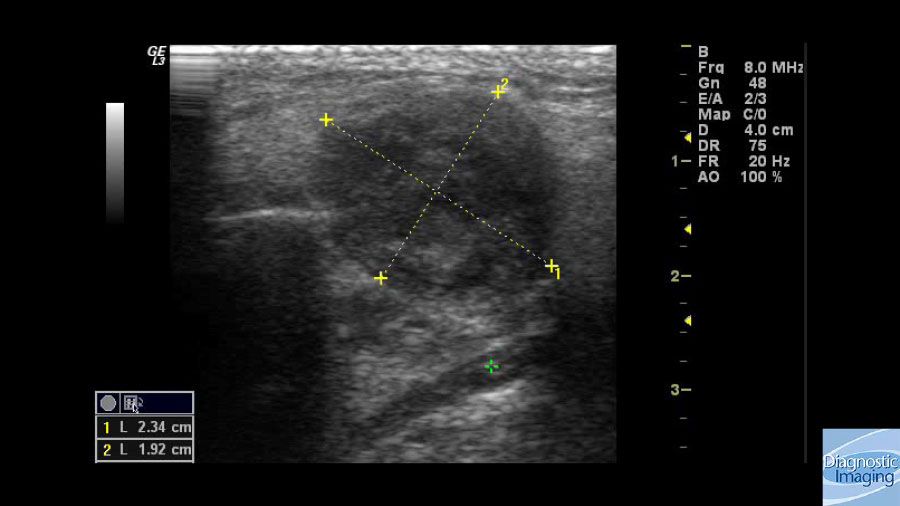

Case History: 24-year-old male with enlarged cervical lymph nodes associated with weight loss and fever.

Case History: 24-year-old male presented with nontender, enlarged cervical lymph nodes associated with weight loss and fever.